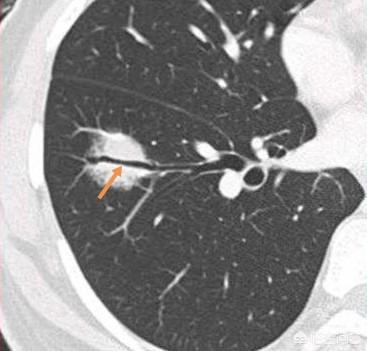

Es handelt sich um einen Fall von chirurgisch bestätigtem Adenokarzinom der Lunge.

Bei soliden Lungenknötchen gibt es dagegen weitaus mehr gutartige als bösartige. Bösartige Lungenknoten weisen in der Regel Grate, Läppchen, Bronchialstümpfe, Stacheln, pleurale Depressionszeichen und Gefäßknäuel auf.